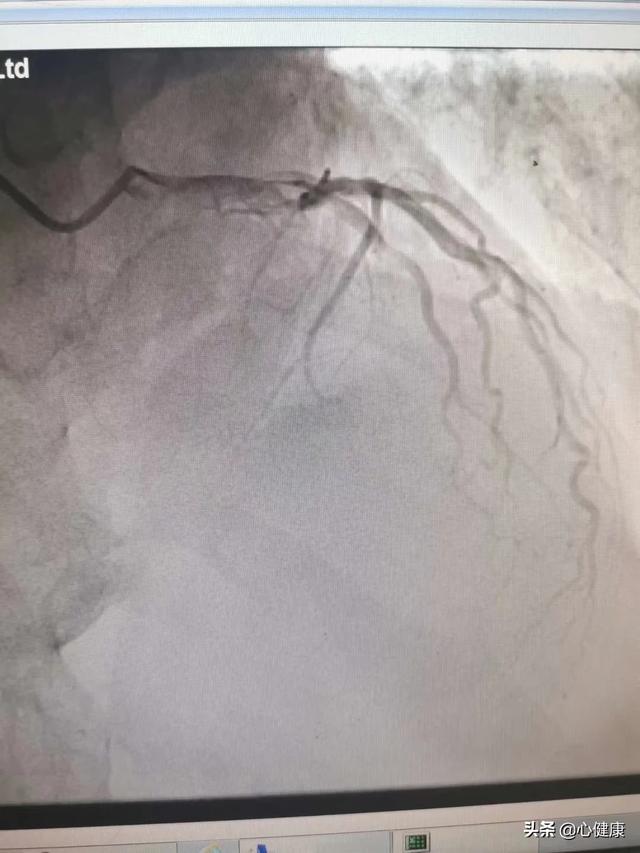

3.冠動脈CTA

腕に留置針を刺し、CT検査を行う際に造影剤を素早く注入し、心臓の血管内に流れ込ませてからCT撮影を行い、最後に冠動脈の三次元画像を背景に冠動脈の狭窄の有無や狭窄の程度を判断します。しかし、協調性、心拍数、呼吸などの要因により、冠動脈造影ほど正確ではない。造影剤腎症を予防するためには、検査後、造影剤が速やかに排泄されるように水分を十分にとることが大切です。腎機能に異常のある人は、この検査を受けられるかどうか決める前に、医師の診断を受ける必要があります。